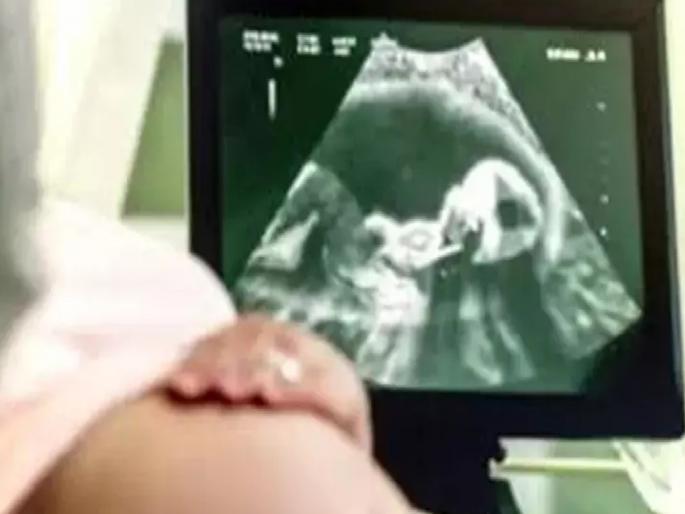

छत्रपती संभाजीनगर/सिल्लोड : दोन वर्षांपासून सिल्लोडच्या जय भवानीनगरमध्ये प्रसुतीगृह व स्त्रीरोग रुग्णालयाच्या नावाखाली आयुर्वेदिक डॉ. रोशन शांतीलाल ढाकरे हा राजरोस अर्भकांची पोटातच हत्या करत करत होता. सिल्लोड पोलिस ठाणे व उपजिल्हा रुग्णालयापासून अवघ्या १ किलोमीटर अंतरावर हे संतापजनक कृत्य सुरू होते. मात्र, प्रशासनाच्या एकाही विभागाला ही बाब कळू शकली नाही, हे विशेष. गारखेड्यात अवैध गर्भलिंग निदान रॅकेटचे धागेदोरे ढाकरेपर्यंत पोहोचल्यानंतर हे रॅकेट उघडकीस आले. ढाकरेसह त्याला मदत करणाऱ्या चार कंपाैंडरांना अटक करण्यात आली. जिल्हाभरात १५ ते २० एजंटांचे जाळे पसरल्याचेही पोलिसांनी सांगितले.

पोलिस गुरुवारी सकाळीच श्री रुग्णालयाजवळ पोहोचले. सविता पकडली जाताच ढाकरेने रुग्णालयाचा बोर्ड काढून, रुग्णालयातील संगणक, शस्त्रक्रियेचे साहित्य, बेड, अन्य सर्व साहित्य हलवून रुग्णालय रिकामे केले होते. अंमलदार दीपक देशमुख, गणेश डोईफोडे, दीपक जाधव, कल्याण निकम, संदीप बिडकर यांनी इमारतीचा दुसरा मजल्यावरील दरवाजा तोडला. तेव्हा आत ढाकरे गोपाल कळांत्रे (रा. सिल्लोड) याच्या वाढदिवसानिमित्त दारूची पार्टी करत असतानाच दोघांच्या मुसक्या आवळल्या. ढाकरेला गर्भपातात मदत करणाऱ्या अन्य कंपाैंडरचा दुसरे पथक शोध घेत होते. अंमलदार राजेश यदमळ, प्रशांत नरवडे, विक्रम खंडागळे, दीपकसिंग यांनी दुसरा कंपाैंडर नारायण पंडित (रा. बाजारसावंगी) ला ताब्यात घेतले. ढाकरेने तो मूळव्याधीचा डॉक्टर असल्याचे सांगून हात झटकले. दुसरीकडे पंडितने मात्र ९ मे रोजीच ढाकरेच्या सांगण्यावरून एक अर्भक त्याच्या शेतात पुरल्याची कबुली दिली आणि पोलिसही थक्क झाले. यादव यांनी तत्काळ रात्री पंडितचे शेत गाठले. तहसीलदार, आरोग्य अधिकाऱ्यांच्या उपस्थितीत पुरलेले अर्भकाचे अवशेष काढले. ढाकरे धारदार ब्लेडच्या वापराने गर्भ बाहेर काढत होता. चार तासांमध्ये गर्भपात करून महिलेला सोडले जायचे. मृतदेह आसपासच्या शेतात पुरायचे.